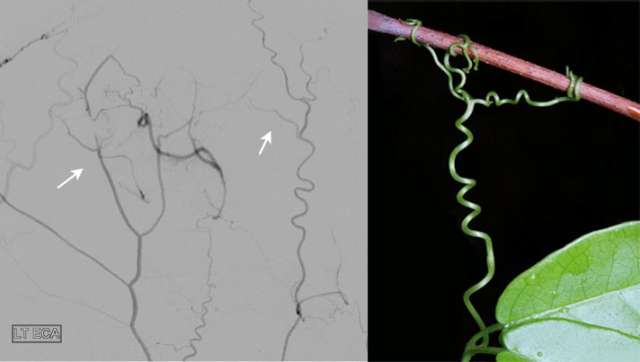

During the surgery to treat these conditions, the arteries from the scalp and the membranes surrounding the brain, called the meninges, are brought into close proximity to the brain. This surgical procedure is named EDAS, short for encephaloduroarteriosynangiosis. EDAS is a very effective treatment for moyamoya and other forms of cerebral arterial narrowing because EDAS stimulates the formation of new vascular connections between the re-routed arteries and the circulation of the brain, bypassing the narrowing of the brain arteries and creating new paths for the supply of oxygen and nutrients.

The figure shows multiple new arteries (arrows) growing from the scalp to the brain after an EDAS surgery in a patient with narrowing of the intracranial arteries. The arteries growing from the scalp resemble the tendrils of a vine reaching to supply additional blood to the brain.